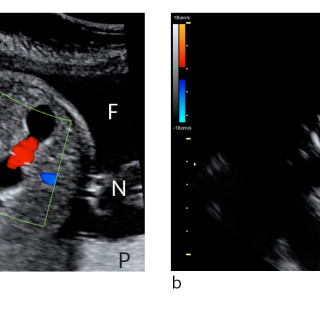

En yngre mann ble innlagt med venstresidige respirasjonsavhengige brystsmerter. Han hadde lett nedsatt allmenntilstand og feber. Det skulle bli et lengre sykehusopphold, der man diagnostiserte en uvanlig årsak til lungeaffeksjon. En tidligere frisk mann i slutten av tenårene ble via legevakt innlagt i sykehus etter ett døgn med venstresidige, respirasjonsavhengige smerter. Ved innkomst hadde han temperatur 37,6 °C, puls 117 slag/min, blodtrykk 104/57 mm Hg, respirasjonsfrekvens 24/min og perifer O2-metning på 94 % uten ekstra oksygentilførsel, og normale forhold ved klinisk undersøkelse...